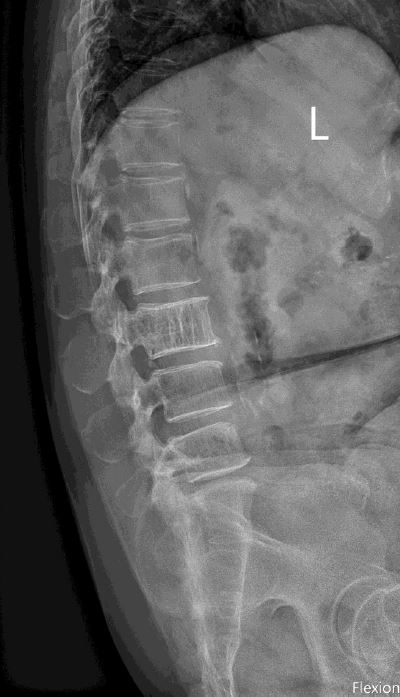

A. Intervertebral disc

B. Ligamentum flavum

C. Posterior longitudinal ligament

D. Facet joint